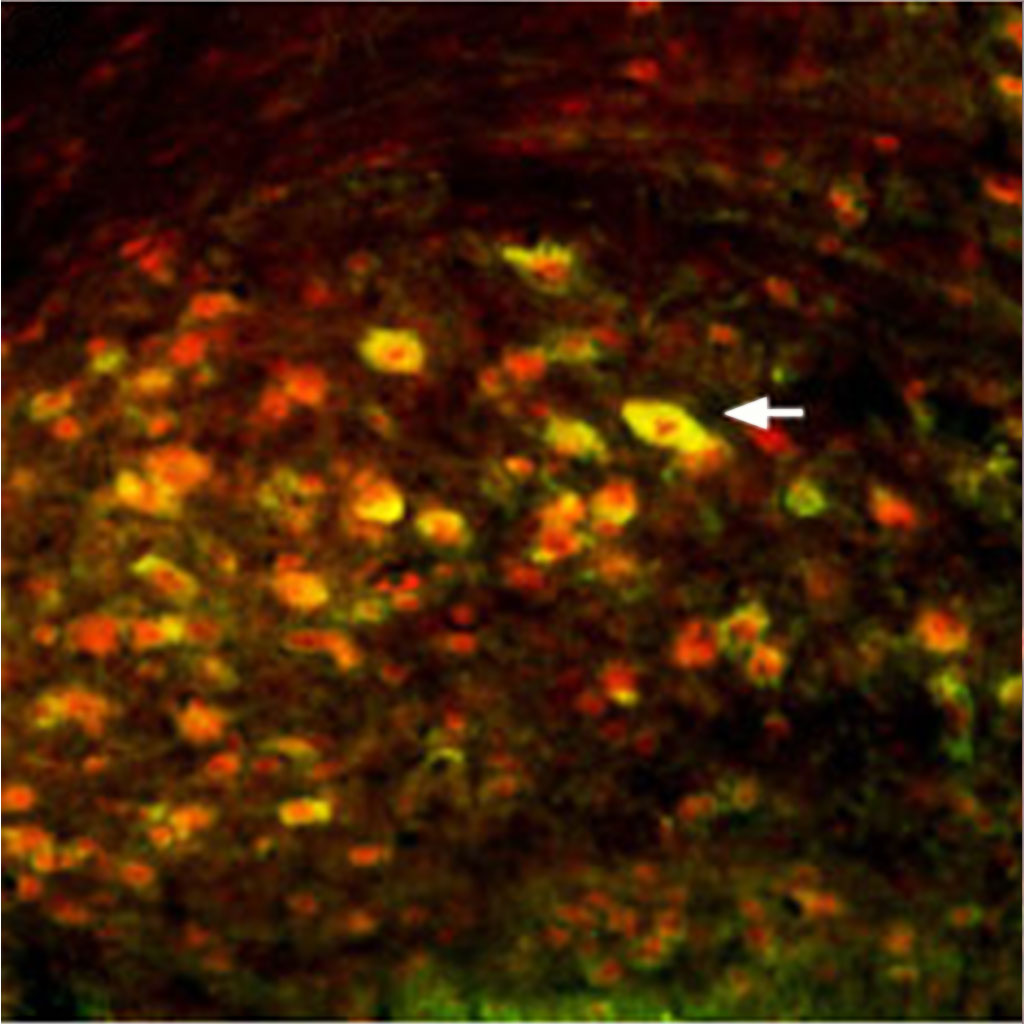

NMDA receptor antibodies are used in research to enable precise and specific detection, localization, and functional analysis of NMDA glutamate receptors. NMDA receptor antibodies are designed to recognize and bind to a specific part of the NMDA glutamate receptor. NMDA receptor antibodies are often conjugated with a detectable molecule, enabling visualization and analysis. Techniques utilizing NMDA receptor antibodies provide valuable insights into the expression patterns, distribution, interactions, and dynamics of NMDA glutamate receptors, leading to a better understanding of their role in neuronal function and neurological disorders.